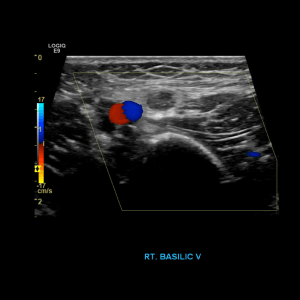

Scan the basilic vein in grey scale, compression, color doppler and spectral doppler

Thrombus of the right basilic vein